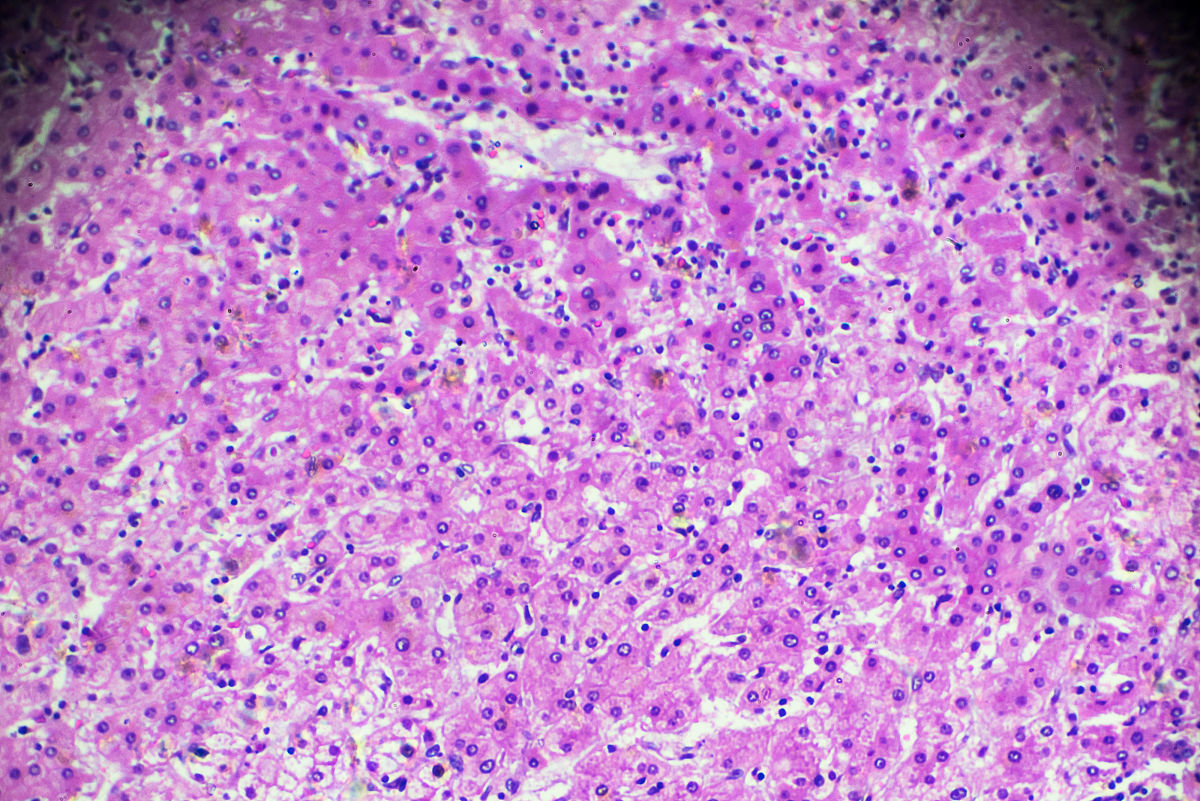

在271例原发性肝癌患者中,有经病理证实的肝细胞癌(HCC)患者250例(92.3%),胆管细胞癌患者19例(7.0%),混合型肝细胞-胆管细胞癌2例(0.7%)。所有患者中‘三阴性’肝癌患者有50例(18.5%),‘非三阴性’肝癌患者221例(81.5%)。单因素分析显示,肿瘤病理类型、有无神经侵犯、MVI风险等级、肿瘤数目是影响患者早期预后的相关因素。两者最显著的差异之一是有11例(22.0%)胆管细胞癌患者表现为‘三阴性’肝。在复发情况方面,至随访截止全组随访时间均为1年,共有109例患者出现复发及死亡。总体上,三阴性肝癌的1年DFS高于非三阴性肝癌患者,但两者没有显著差异(P>0.05)。